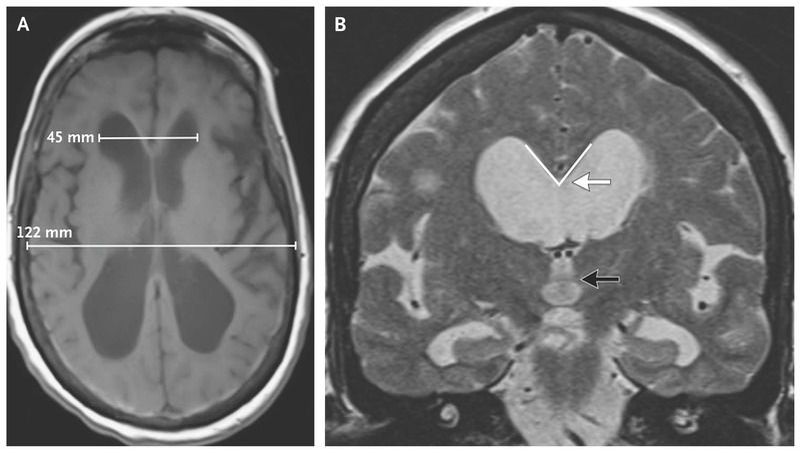

A 70-year-old woman presented to the neurology clinic with a 2-year history of gait disturbance, cognitive impairment, and urinary incontinence. Examination revealed a Mini–Mental State Examination (MMSE) score of 12 (on a scale of 0 to 30, with higher scores representing better performance) and a short-stepped, narrow-based, nonataxic gait. The patient walked 7.6 m in 31 seconds (Video 1). Magnetic resonance imaging revealed ballooning of the ventricles, with an Evan’s ratio (the ratio of the width of the frontal horns of the lateral ventricles [45 mm in this patient] to the internal diameter of the skull [122 mm]) of 0.37 (upper limit of the normal range, 0.31) (Panel A). The callosal angle (Panel B, white arrow) — the angle (outlined in white) between the lateral ventricles measured at the level of the posterior commissure (black arrow) on a coronal plane perpendicular to a line between the anterior and posterior commissures — was less than 90 degrees (reference range, 100 to 120). A lumbar puncture revealed a normal opening pressure, a finding consistent with normal-pressure hydrocephalus. Normal-pressure hydrocephalus classically manifests with urinary incontinence, gait disturbance, and dementia. Surgical shunting of cerebrospinal fluid is the main treatment method. A ventriculoperitoneal shunt was placed, which led to a marked improvement in the patient’s gait 6 months after shunt placement, she walked 7.6 m in 6 seconds. The MMSE score increased to 20 points at 1 month, with resolution of urinary incontinence, and increased to 28 points at 6 months.